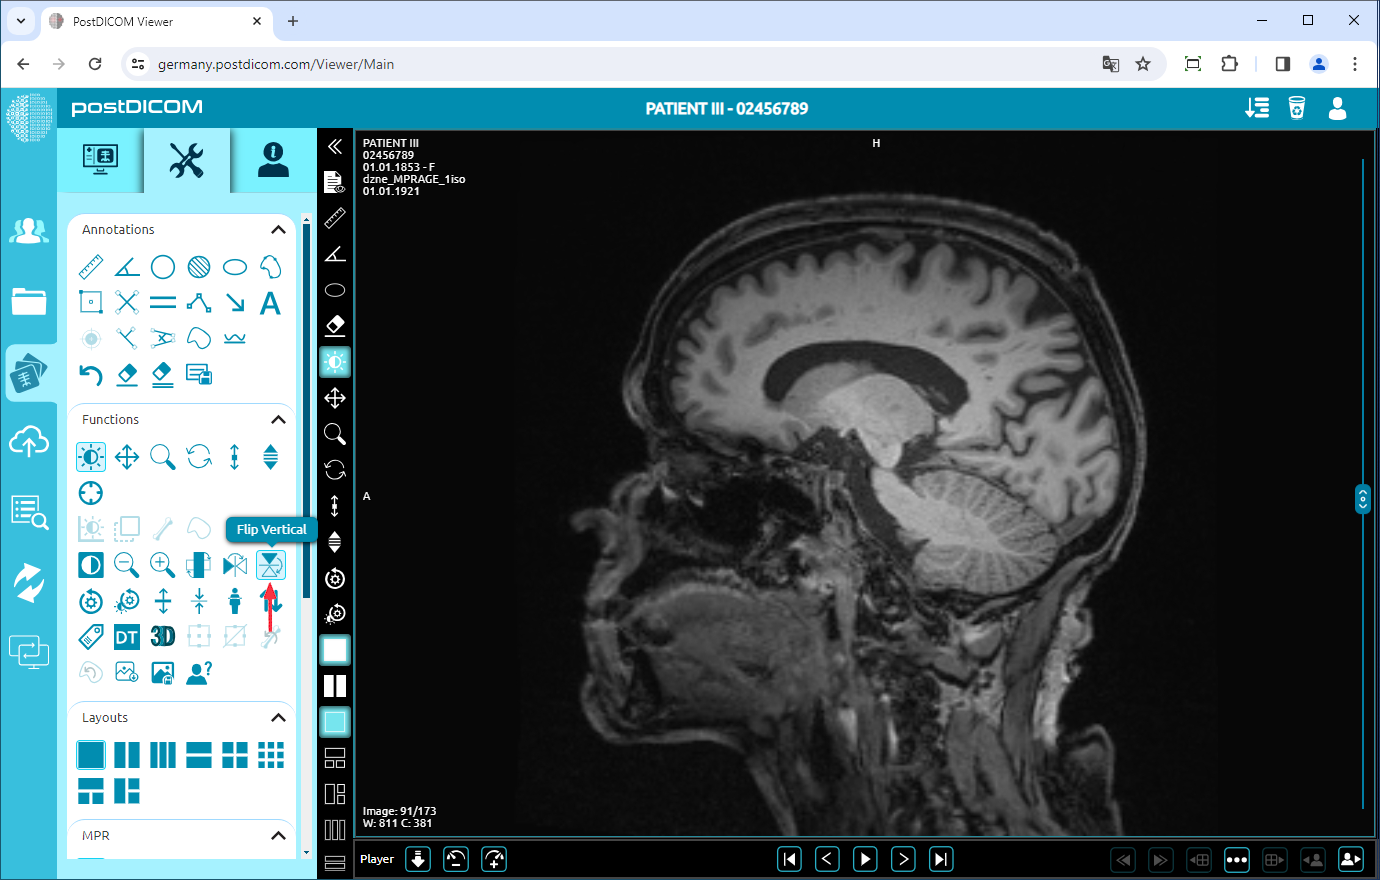

Flip Vertical

Click on the “Flip Vertical” icon on the left side of the page to flip the image vertically.

Once you have clicked, you will see the vertical mirror view of your image on the viewport.